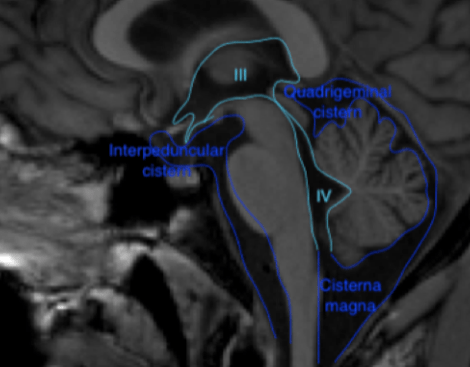

As a medical student the first thing about the brain I knew by heart was the ventricular system. It was so easy to remember: *Cerebrospinal fluid (CSF) gets produced by the choroid plexus in the lateral ventricles -> flows via the foramen of Monro to the 3rd ventricle -> from the 3rd ventricle via the aqueduct to the 4rd ventricle and then via L-Lateral foramina of Luschka and a M-Median foramen of Magendie to the subarachnoid space. *Granulations of Pacchioni in the subarachnoid space resorb CSF.

Figure 1 Coronal (above) and sagittal (below) T1 weighted images showing the lateral ventricles (lat), third (III) and fourth ventricle (IV) and several subarachnoid cisterns. The temporal horn of the lateral ventricle is anatomically close to the subarachnoid space, more specific the choroid fissure.

The brain and spinal cord are surrounded by 3 layers of connective tissue: (1) the pia, lying direct against the parenchyma (2) the arachnoid, which is an avascular layer bridging the cortical sulci and bridging the distance to the skull and (3) the dura mater consisting of an outer periosteal layer and an inner meningeal layer. The arachnoid and the space between the arachnoid and pia houses CSF. The widenings in the subarachnoid space called cisterns seemed like topography: something to memorize without the need for deeper knowledge.